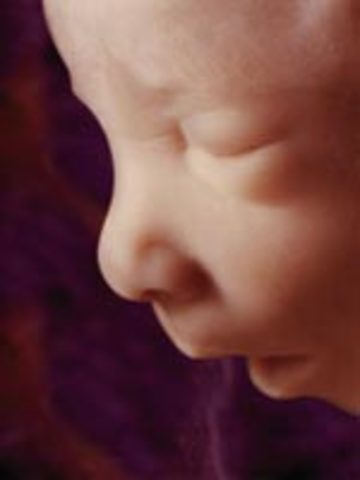

• Week 14

Week 14

The fetus in now 3.5 inches long. The face is starting to become more visible and the baby is peeing. Bones are getting stronger and harder and hair is starting to develop.